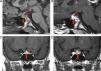

RM de región sellar al diagnóstico. A) Corte sagital sin contraste: ausencia de la señal normal de la neurohipófisis, aumento del volumen de la adenohipófisis (flecha gruesa) y engrosamiento del infundíbulo (flecha fina). B) Corte sagital con contraste: importante realce en infundíbulo (flecha fina) y tuber cinereum. C) Corte coronal con contraste: heterogeneidad de señal de la adenohipófisis (flecha gruesa) asociada a llamativo engrosamiento del tallo pituitario (flecha fina). D) Corte coronal con contraste: realce heterogéneo en la adenohipófisis (flecha gruesa).

Niña de 9 años que consulta por poliuria y polidipsia bruscas (5-6 l/día) de 2 meses de evolución, sin pérdida de peso, alteración subjetiva del crecimiento, cefalea, alteraciones visuales, galactorrea ni otra sintomatología. Exploración física, incluido fondo de ojo, normal con talla 134cm (–0,7 DE), IMC 19,8kg/m2 (0,3 DE), estadio puberal 1 Tanner y talla diana 162,5cm (–0,2 DE). Estudio analítico: marcadores tumorales sanguíneos y anticuerpos-antihipófisis negativos; función hipofisaria con déficit de hormona antidiurética en el test de restricción hídrica, respuesta patológica de hormona crecimiento (GH) en 2 tests farmacológicos de estímulo (test de hipoglucemia insulínica y ornitina con picos de 2,6 y 2,2ng/ml, respectivamente), IGF1 233,9ng/ml (VN=117-771) e IGFBP3 1,75ng/ml (VN=1,58-3,99), sin otros déficits hormonales; líquido cefalorraquídeo con bioquímica, citología y marcadores tumorales normales. Estudio radiológico: radiografía lateral craneal y gammagrafía ósea sin alteraciones; RM con aumento del volumen adenohipofisario, engrosamiento y marcado realce del infundíbulo y ausencia de señal hiperintensa de neurohipófisis (fig. 1). Con el diagnóstico de presunción de infundíbulo-hipofisitis-linfocítica (INHL) se realizó seguimiento clínico estrecho con tratamiento específico para la diabetes insípida (DI) y controles periódicos de RM craneal para evaluar la necesidad de completar estudio con biopsia. A los 3 meses se detectó mejoría radiológica, con normalización del tamaño de la adenohipófisis, discreto engrosamiento del tallo y persistencia de ausencia de la señal normal neurohipofisaria (fig. 2.1 y 2.2). El déficit bioquímico de GH revirtió en el test de estímulo realizado a los 6 meses, siendo el crecimiento e inicio y posterior desarrollo puberal normales, con talla adulta 164cm (0 DE), menarquia a los 126/12 años y posteriores reglas regulares. La imagen patológica de hipófisis y tallo se normalizó al año de la seguimiento y 10 años después se mantiene normal, permaneciendo únicamente la ausencia de señal neurohipofisaria (fig. 2.2). Sigue precisando tratamiento con vasopresina para controlar la DI.